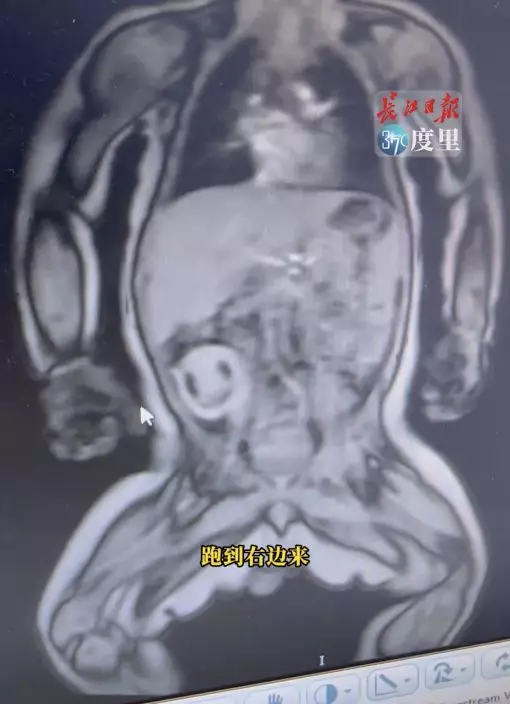

據內媒報道,湖北武漢一名黎姓孕婦在懷孕30周時進行產前檢查,怎料卻發現下腹部有一枚6公分大小的囊腫,經進一步確認後得知其為同卵雙胞胎,但不幸的是其中一胎因發育不良,意外地進入另一胞胎的睪丸,轉變為「寄生胎」。

今年6月,該名孕婦成功誕下一名男嬰(化名為銘銘),然而在進行例行檢查時,醫生發現該寄生胎已從左側睪丸轉移至右側,且開始出血壞死。直至10月中,武漢大學中南醫院婦兒醫院的小兒外科專家成功地在1小時內將寄生胎與主體分開,而銘銘目前也已康復出院。

醫學專家指出「胎中胎」的全球發生概率約為50萬分之一,而位於睪丸的罕見寄生胎案例僅有數宗已知報告。